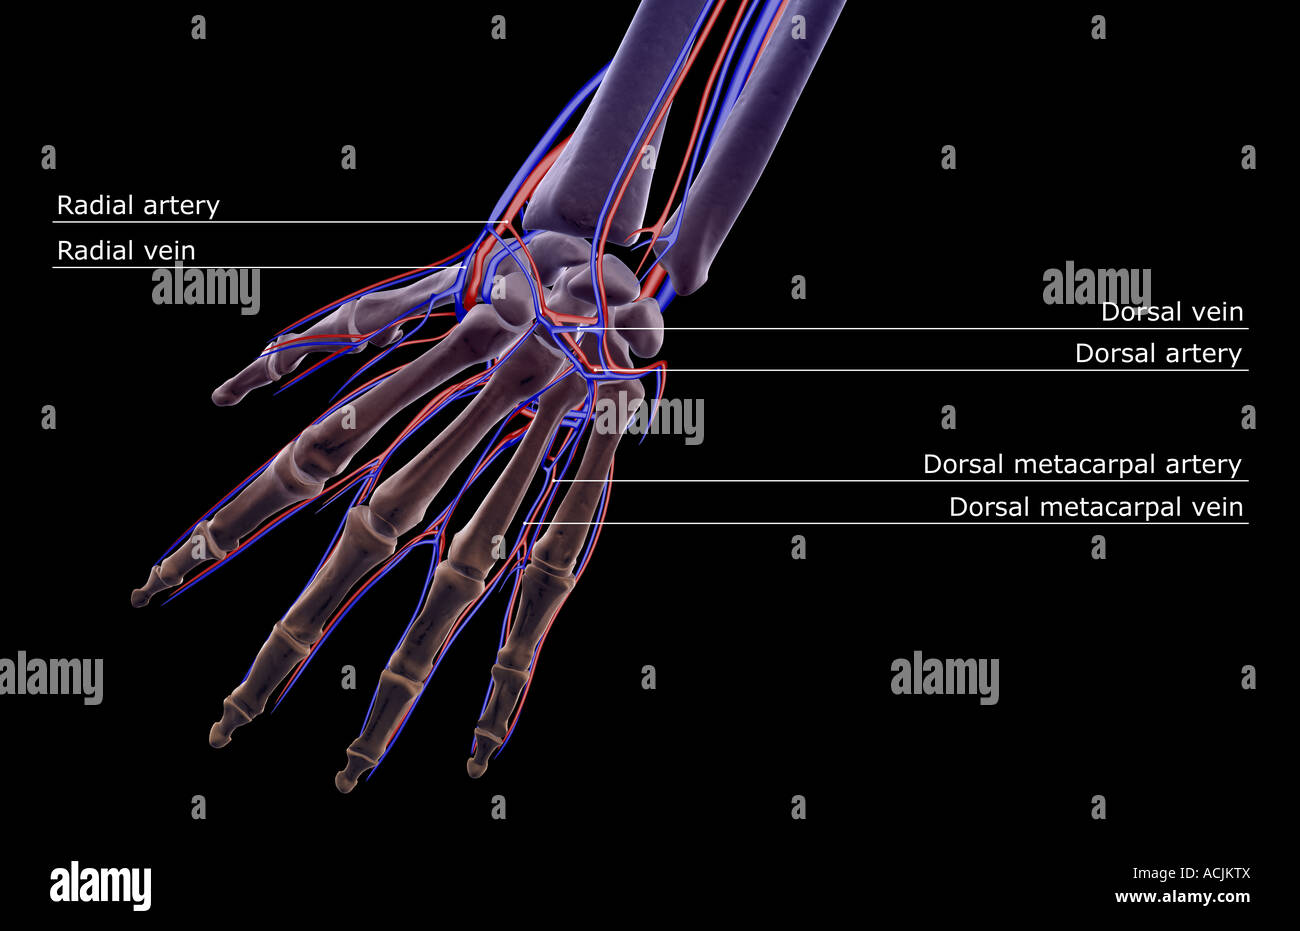

The blood supply of the hand Stock Photohttps://www.alamy.com/image-license-details/?v=1https://www.alamy.com/stock-photo-the-blood-supply-of-the-hand-13171609.html

The blood supply of the hand Stock Photohttps://www.alamy.com/image-license-details/?v=1https://www.alamy.com/stock-photo-the-blood-supply-of-the-hand-13171609.htmlRFACJKTX–The blood supply of the hand